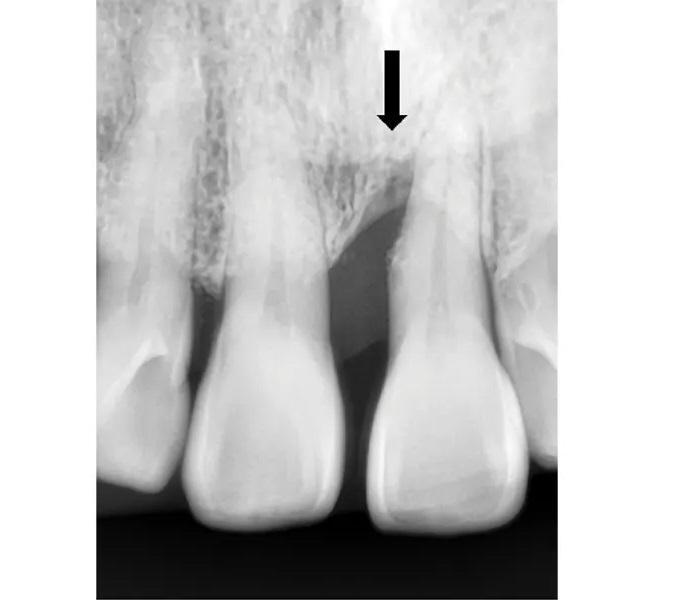

65-летняя некурящая пациентка с пародонтитом обратилась с костным дефектом на мезиальной поверхности верхнего левого центрального резца (зуб № 2.1) (Фото 1 и Фото 2). Зарегистрированный индекс подвижности (по Грейсу и Смейлсу) составил 2 степень, т.е. движение в вестибуло-лингвальном направлении на 1–2 мм. Во время процедуры пластики был отслоен слизисто-надкостничный лоскут, обнажен глубокий пародонтальный дефект (Фото 3 и Фото 4). Аутогенная кость была взята из ветви нижней челюсти и смешана в соотношении 1:2 с ДМБК (покрытый ОКФ, 100% губчатая кость) (Ti-oss, Chiyewon Co. Ltd.; распространяется как creos xenoform, Nobel Biocare). Полученный материал был смешан с высококонцентрированными тромбоцитами, полученными путем дополнительного центрифугирования БоТП (упоминается как концентраты тромбоцитов в протоколе, адаптированном автором), к которым были добавлены тромбин и кальций для образования коагулированной массы (Фото 5), использованной для заполнения дефекта (Фото 6). Показано, что тромбин и кальций in vitro и in vivo активируют тромбоциты для высвобождения факторов роста, тем самым стимулируя остеобласты, усиливая ангиогенез и способствуя миграции клеток.

Фото 1. Предоперационный рентгеновский снимок. Стрелка указывает на пародонтальный дефект у зуба № 2.1.